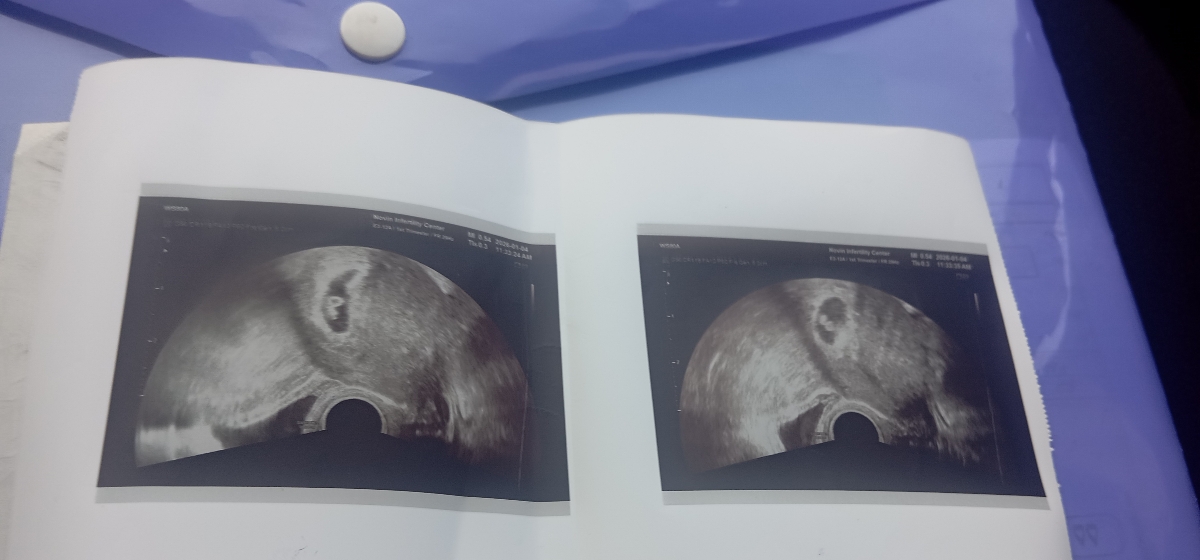

میگ من اولین سونو رفتم دوقلو بود ولی دوباره گفت ۱۰ روز دیگ برم دلیلش چیه

گفتن ۶ هفته ام شنبه این هفته رفتم

چون خود مرکز رفتم چیزی جز این عکس ندادن بهم

سلام من وقتی رفتم سونو هردو قلبشون تشکیل شده بود ولی دکتر گفت تا ده هفته احتمال اینکه ی قل یهو رشد نکنه هس باید سونو برم تا ده هفته دوبار دیگه هم رفتم و الان دوقلوهام بغلم هستن مبارکت باشه عزیزم

سلام عزیزم روال ای وی اف اینجوری هست توی این سونو فقط ساک رو میبینه تو سونو بعدی انشاءالله قلب

آره ای وی اف اول ساک رو چک میکنن ک خدا رو شکر قلب هم داشته اما صداشو نمیزارن چون کوچیکه برای منم همینجوری بود حدود دو هفته بعد برای سونوی هشت هفته رفتم سونوگرافی معمولی دیگه واژینال نمیخواست

قلب جنین تشکیل شده بود گلم 💝❤️💚

اره هست صدای قلبشو گذاشت برات

سلام گلم آها منم رفتم گوفت همچی خوب دوتا نی نی نشونم دادم گفت دوهفته دیگ بیا برام دعا صدا قلبشون بشنوم